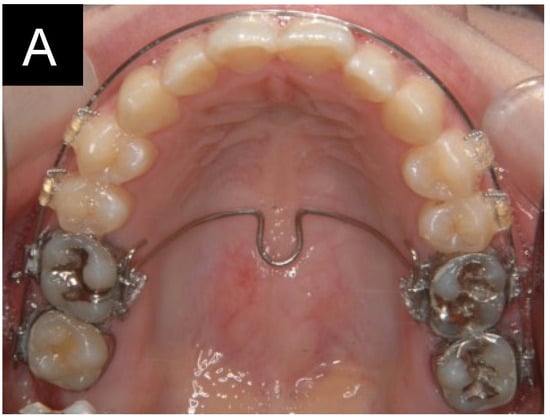

All patients were treated with a preadjusted edgewise appliance using brackets with a nominal slot size of 0.018 in (Crystabrace 7; Dentsply, Tokyo, Japan). Mini-screws (AbsoAnchor, Dentos Inc., Daegu, Republic of Korea; 1.3 mm in diameter, 5.0–7.0 mm in length) were placed in the buccal interdental regions between the first and second molars or the second premolar and first molar (Figure 1). Since interdental space and cortical bone thickness are major factors for the stability of mini-screws [,], the placement sites of the mini-screws were determined based on these two factors measured from medical CT images. Fourteen mini-screws were placed in the buccal alveolar bone between the maxillary first and second molars. Six mini-screws were placed between the second premolar and the first molar. A continuous archwire (0.016 × 0.022-inch stainless steel) was placed in the posterior teeth, and a transpalatal arch was placed on the maxillary first molars. Elastics were engaged between the mini-screws and the continuous archwire to intrude the maxillary posterior teeth. The intrusion force generated by the elastics was approximately 200 g per side. The mean treatment period of molar intrusion was 7.1 months, and subsequent treatment, including the alignment of the maxillary anterior teeth, was continued. The duration of active treatment was 3.1 ± 0.68 years.

Figure 1.

Mechanics for intrusion of the maxillary molars. (A) occlusal view. (B) lateral view. (C) mini-screw.